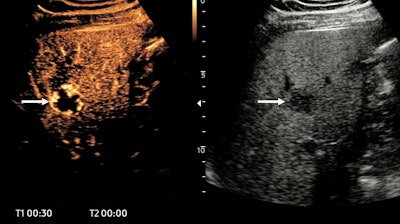

In a 47-year-old man with upper abdominal pain, ultrasound shows a fatty liver and an atypical lesion (arrow). The CEUS examination answered the question in 30 seconds -- this is a hemangioma, with classical pathognomonic peripheral globular enhancement (arrow). It’s a “slam-dunk” diagnosis: no further imaging, no further costs, and the patient knows immediately that this is benign. Figure courtesy of Prof. Paul Sidhu.